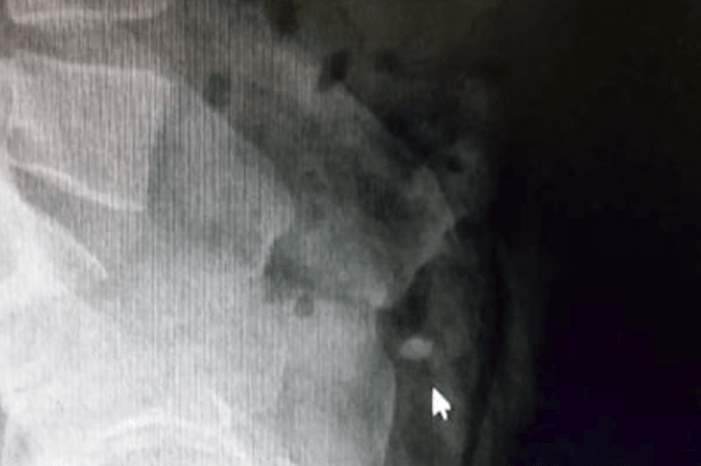

وأمرت الشرطة بنقل السارق إلى المستشفى، من أجل إجراء عملية جراحية للعثور على الخاتم، ما لم يعد الأيرلندي الخاتم بـ"الطريقة الطبيعية".

وتابعت وسائل إعلام تركية "رحلة" الخاتم، لحظة بلحظة لمدة يومين كان خلالها اللص ينتظر في المستشفى بعدما تناول أدوية تسهّل الإخراج، وذلك تحت حراسة الشرطة.

وقد قفز مرارا في المستشفى لتحريك الخاتم في أحشائه لمدة 36 ساعة، لكن جهوده كانت بلا جدوى، وبعد ذلك لجأت السلطات إلى استخراج الألماس عبر عملية جراحية.